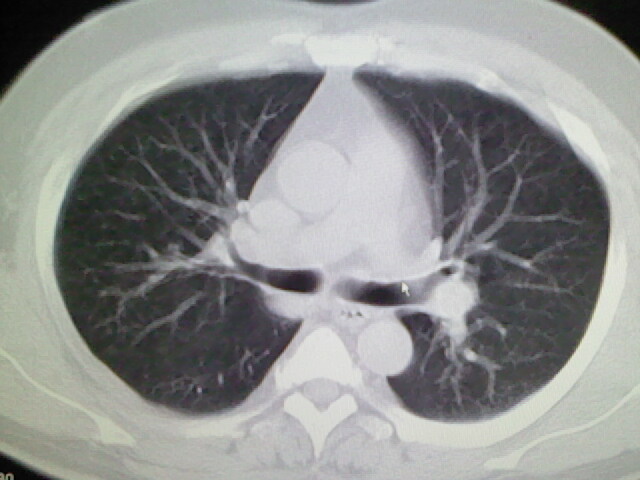

标题: CT17932:临床怀疑肺栓塞 [打印本页]

标题: CT17932:临床怀疑肺栓塞

男,34岁,自觉右侧胸痹,胸闷3天余

肺纹理分布较均匀,暂不提示肺梗塞

未见明显异常。图像上看此患者比较肥胖,建议查下心超